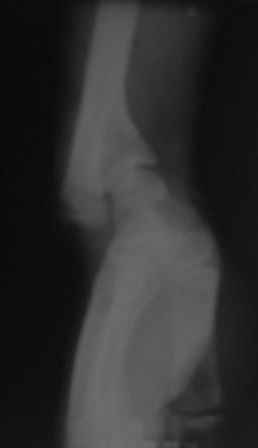

Под рукой оказалась минирентген локтевого сустава, где можно увидеть cubita valga(последствие надмышелкового перелома).

PICT0009.JPG

8KB (8509 bytes)